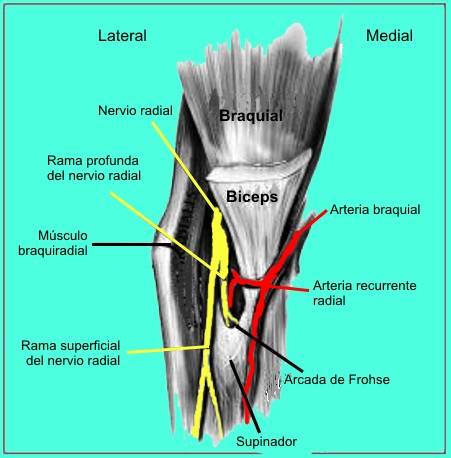

- El sitio más frecuente de compresión es en la

parte proximal del antebrazo en el área donde el músculo

supinador forma un arco fibroso por donde penetra la rama

interosea posterior (la llamada arcada de Fröhse).

Síndrome del túnel radial

Este diagnóstico es muy controvertido

y se piensa que es el resultado del uso excesivo. Algunos autores

creen que el síndrome del túnel radial puede representar un síndrome

temprano de la compresión del nervio interóseo posterior (rama

profunda del nervio radial). Los sitios de compresión incluyen las

bandas fibrosas insertadas a la articulación radiocapitelar, vasos

recurrentes radiales, el origen tendinoso del extensor radial corto

del carpo, el origen tendinoso del supinador (es decir, arcada de

Frohse), y engrosamientos fibrosos dentro y en el margen distal del

supinador.

Síndrome del nervio interóseo

posterior

La etiología del síndrome del nervio

interóseo posterior es similar a la del síndrome del túnel radial.

La compresión se cree que se producen después de despegar las ramas

a los extensores radiales de la muñeca y el nervio sensitivo radial.

Después de salir del supinador, el nervio puede ser comprimido antes

de que se bifurca en ramas medialea y laterales, causando una

parálisis completa de los extensores digitales y desviación

dorsorradial de la muñeca secundaria a parálisis del extensor

cubital del carpo.

Si se produce la compresión después de que se bifurque el nervio, se

produce parálisis selectiva de los músculos, dependiendo de qué rama

se tratara. La compresión de la rama medial causa parálisis de los

extensor cubital del carpo, extensor del meñique, y extensor común

de los dedos. La compresión de la rama lateral causa parálisis del

abductor largo del pulgar, extensor corto del pulgar, extensor largo

del pulgar, extensor y propio del índice. Más comúnmente, el

atrapamiento se produce en el borde proximal del supinador.